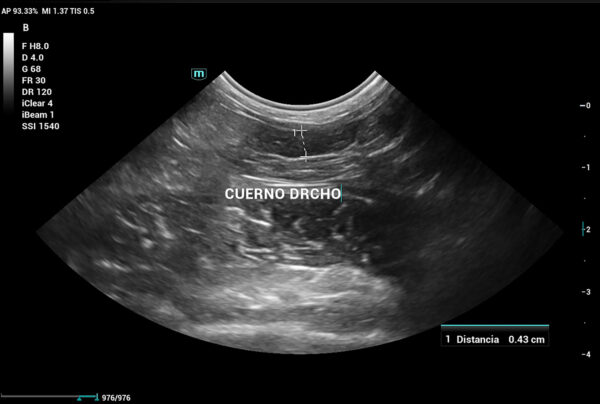

Se realiza ecografía abdominal, que evidencia que aún cuenta con cuernos uterinos (imagen 6), lo que confirma la ovariectomía (no ovariohisterectomía). Por este motivo, se decide enviar una muestra de plasma sanguíneo a un laboratorio externo para evaluar los niveles de 17β-estradiol, dado que en ecografía no se logra distinguir con claridad un remanente ovárico.

En conejas esterilizadas o con sospecha de remanente ovárico, valores de 17β-estradiol por encima de 10 – 20 pg/mL pueden indicar la presencia de tejido ovárico funcional residual (debería presentar aproximadamente la misma concentración que un conejo macho). En el caso de esta coneja, el resultado fue de 62 pg/mL, lo cual confirma la presencia de remanente ovárico, dado que hay producción de estrógenos. En este caso, fue suficiente con la medición de estradiol para confirmar el diagnóstico, aunque en otras ocasiones podríamos utilizar la medición de hormona antimulleriana como alternativa.

Además de las pruebas descritas, y dado que los tutores comentaban que la coneja dejaba de practicar la cecotrofia en algunos momentos, también se realiza un estudio radiográfico de columna, en el cual no existen alteraciones de relevancia que justifiquen un dolor de columna que pueda explicar la ausencia de cecotrofia. Ante el resultado de todas las pruebas realizadas, se decide llevar a cabo una histerectomía.

En las pacientes sometidas a ovariectomía sin histerectomía, debemos tener en cuenta que aún existe riesgo de que padezcan algún tipo de patología uterina que pueda desarrollarse sin ovarios, así como actividad uterina residual, persistencia de conductas hormonales y de síndrome del remanente ovárico, como en el caso presentado.